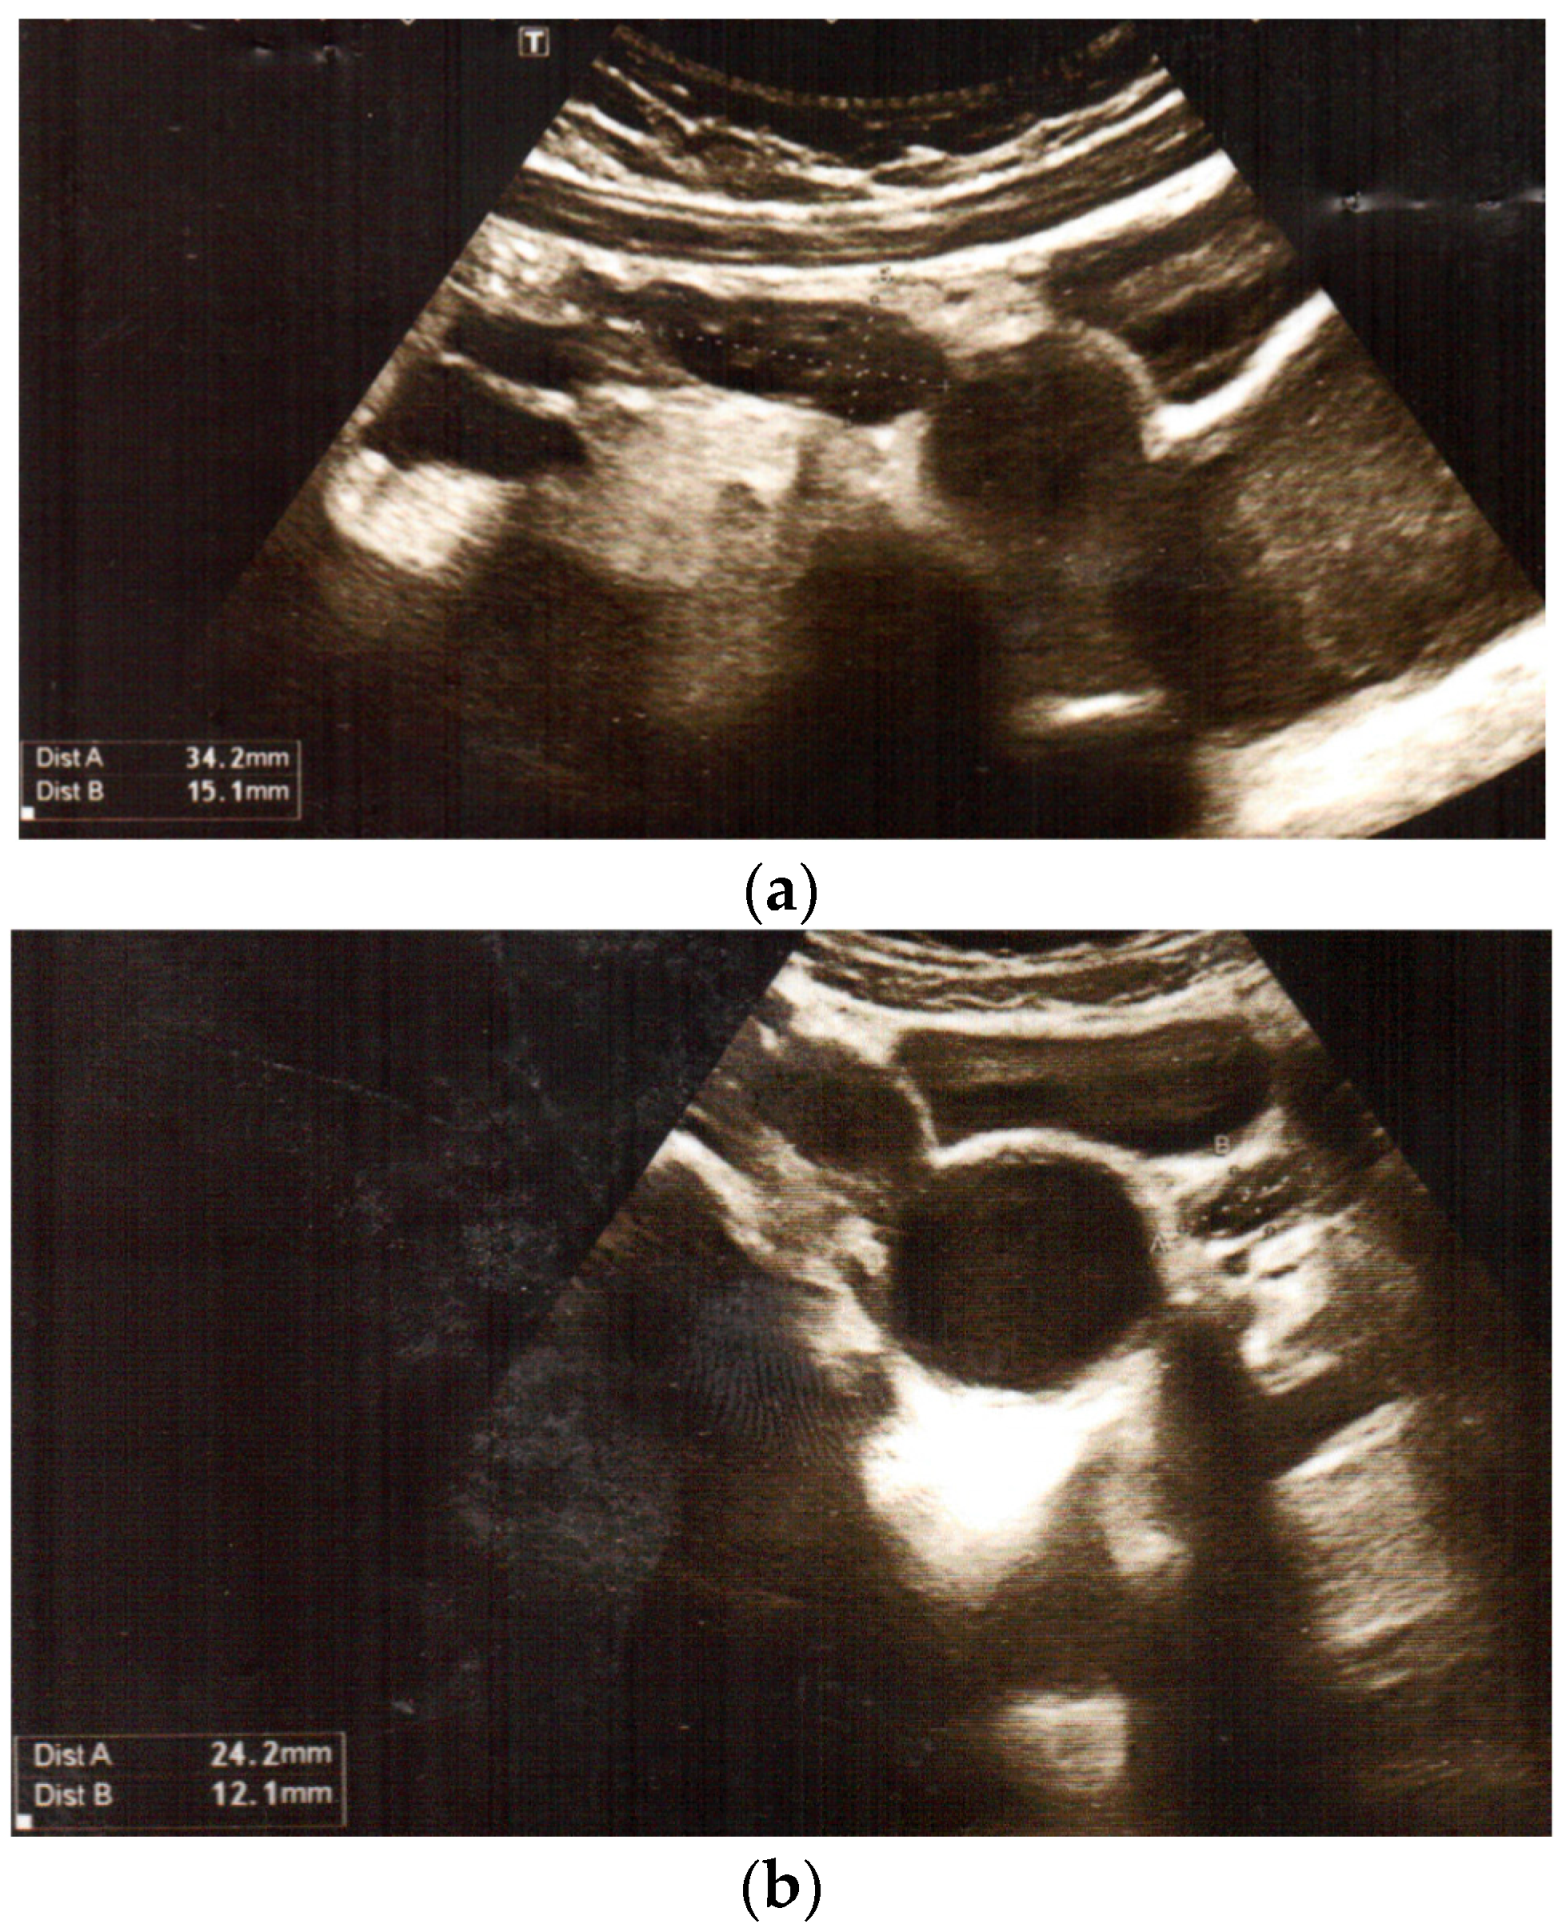

We present the medical history of a 16.5-year-old girl who underwent urgent surgery at the age of 12 years. The girl was admitted to the Department of Urology due to complaints of severe abdominal pain on the sixth day of menstruation, with bladder pressure. There was no reaction to analgetic or spasmolytic medications. Transabdominal pelvic ultrasound examination revealed duplication of the uterus (uterus with right-sided oval hypoechogenic structure) and vagina, with a right vagina of 52 mm × 58 mm × 10 mm filled with blood (haematocolpos), normal ovaries (Figure 1). Abdominal ultrasound showed right renal agenesis with normal left kidney and ureter, and constricted bladder.

Figure 1.

Transabdominal pelvic ultrasound at the time of diagnosis: (a,b) duplication of uterus: uterus with right-sided oval hypoechogenic structure, and normal ovaries (c,d) duplication of vagina, with haematocolpos on the right side.